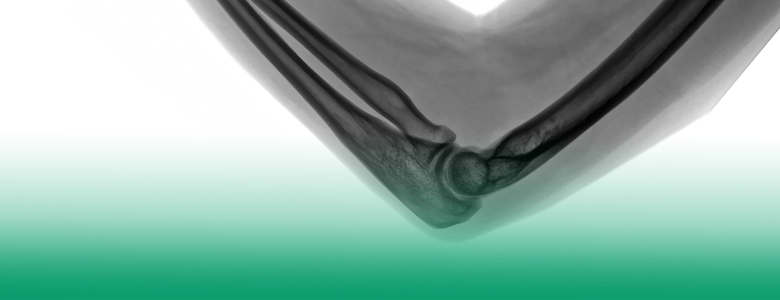

Orthopedy Rumah Sakit Satya Negara Sunter berfokus pada perawatan sistem muskuloskeletal, yaitu penanganan gangguan pada sistem tulang, otot, saraf, sendi, ligamen, tendon dan struktur terkait yang mengganggu fungsi dan aktifitas sehari-hari, akibat dari cedera, infeksi, tumor, dan lain sebagainya.

Arthroscopy

Prosedur ortopedi dengan menggunakan alat artroskop yang dilengkapi dengan kamera yang dimasukkan melalui lubang sayatan yang sangat kecil untuk menampilkan gambaran sendi yang dapat dilihat pada monitor khusus, sehingga proses perbaikan sendi dapat berjalan akurat dengan luka yang sangat minimal dalam waktu yang singkat.